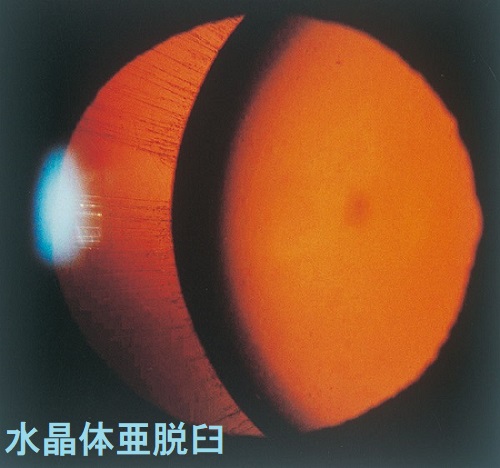

マルファン症候群の身体的特徴として、高身長で四肢の指が長い、胸郭の変形、眼の水晶体亜脱臼などがあります。

マルファン症候群で特に問題になるのが大動脈壁の脆弱性で、

- 大動脈瘤、急性大動脈解離がおこると命にかかわります

通常の急性大動脈解離は60歳以上の高齢者に多い病気ですが、マルファン症候群では20歳-30歳代で発症することが多い。